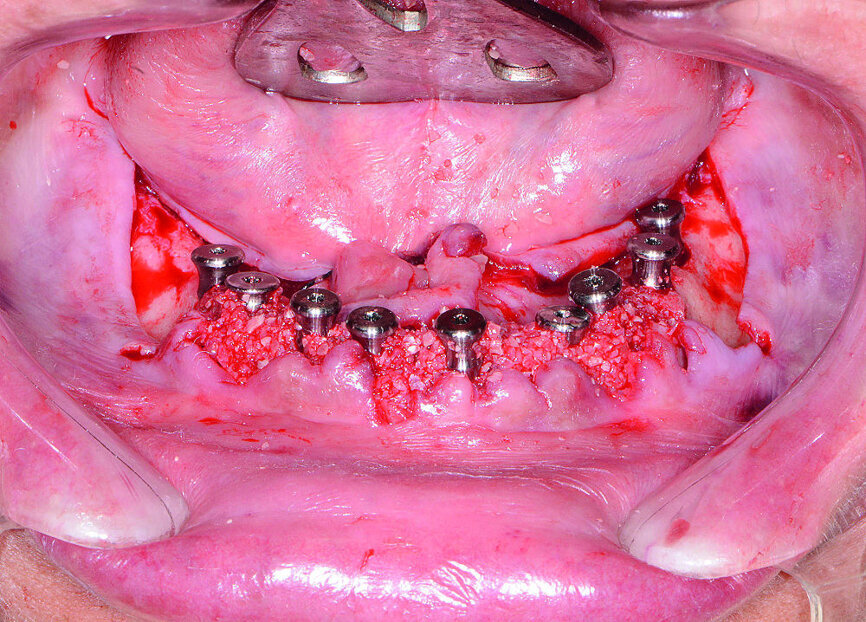

Ensuite, les dents mandibulaires, qui étaient irrécupérables (Fig. 13), ont été extraites à l’aide du davier Physics Forceps (GoldenDent), un lambeau a été décollé et une alvéoloplastie réalisée. Un guide chirurgical à appui osseux a été mis en place pour vérifier l’emplacement et l’angulation des ostéotomies implantaires (Fig. 14). Étant donné que les implants coniques Hahn sont pourvus d’un filetage auto-taraudeur, les filets profonds et tranchants, pénètrent dans les parois des sites alvéolaires et permettent de maintenir l’implant dans la position appropriée, par rapport à la paroi linguale. À la suite du nivellement osseux, on pouvait s’attendre à un gonflement des tissus, et des piliers de cicatrisation de 5 mm de hauteur ont donc été connectés aux implants de l’arcade mandibulaire (Fig. 15). Les prothèses immédiates ont été rebasées avec un matériau souple (Mucopren, de Kettenbach) afin de les insérer sur les piliers de cicatrisation, dont la forme en sablier et les zones rétentives assurent un degré de rétention qui améliore la fonction dentaire pendant la cicatrisation (Fig. 16).

Fig 15 Implants et coiffes de cicatrisation entourés du matériel de greffe